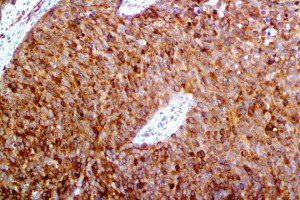

It is the ICU physician who is most likely to witness one of the deadliest manifestations of the abnormal immunological response, the cytokine storm syndrome (CSS). This response is also referred to by some as the cytokine release syndrome (CRS). CSS is characterized by continuous activation and expansion of macrophage and lymphocyte populations, which secrete large amounts of cytokines, causing the cytokine storm. This massive cytokine release is akin to hemophagocytic lymphohistiocytosis (HLH) disease, a syndrome characterized by initial unchecked and persistent activation of cytotoxic T lymphocytes and NK cells.